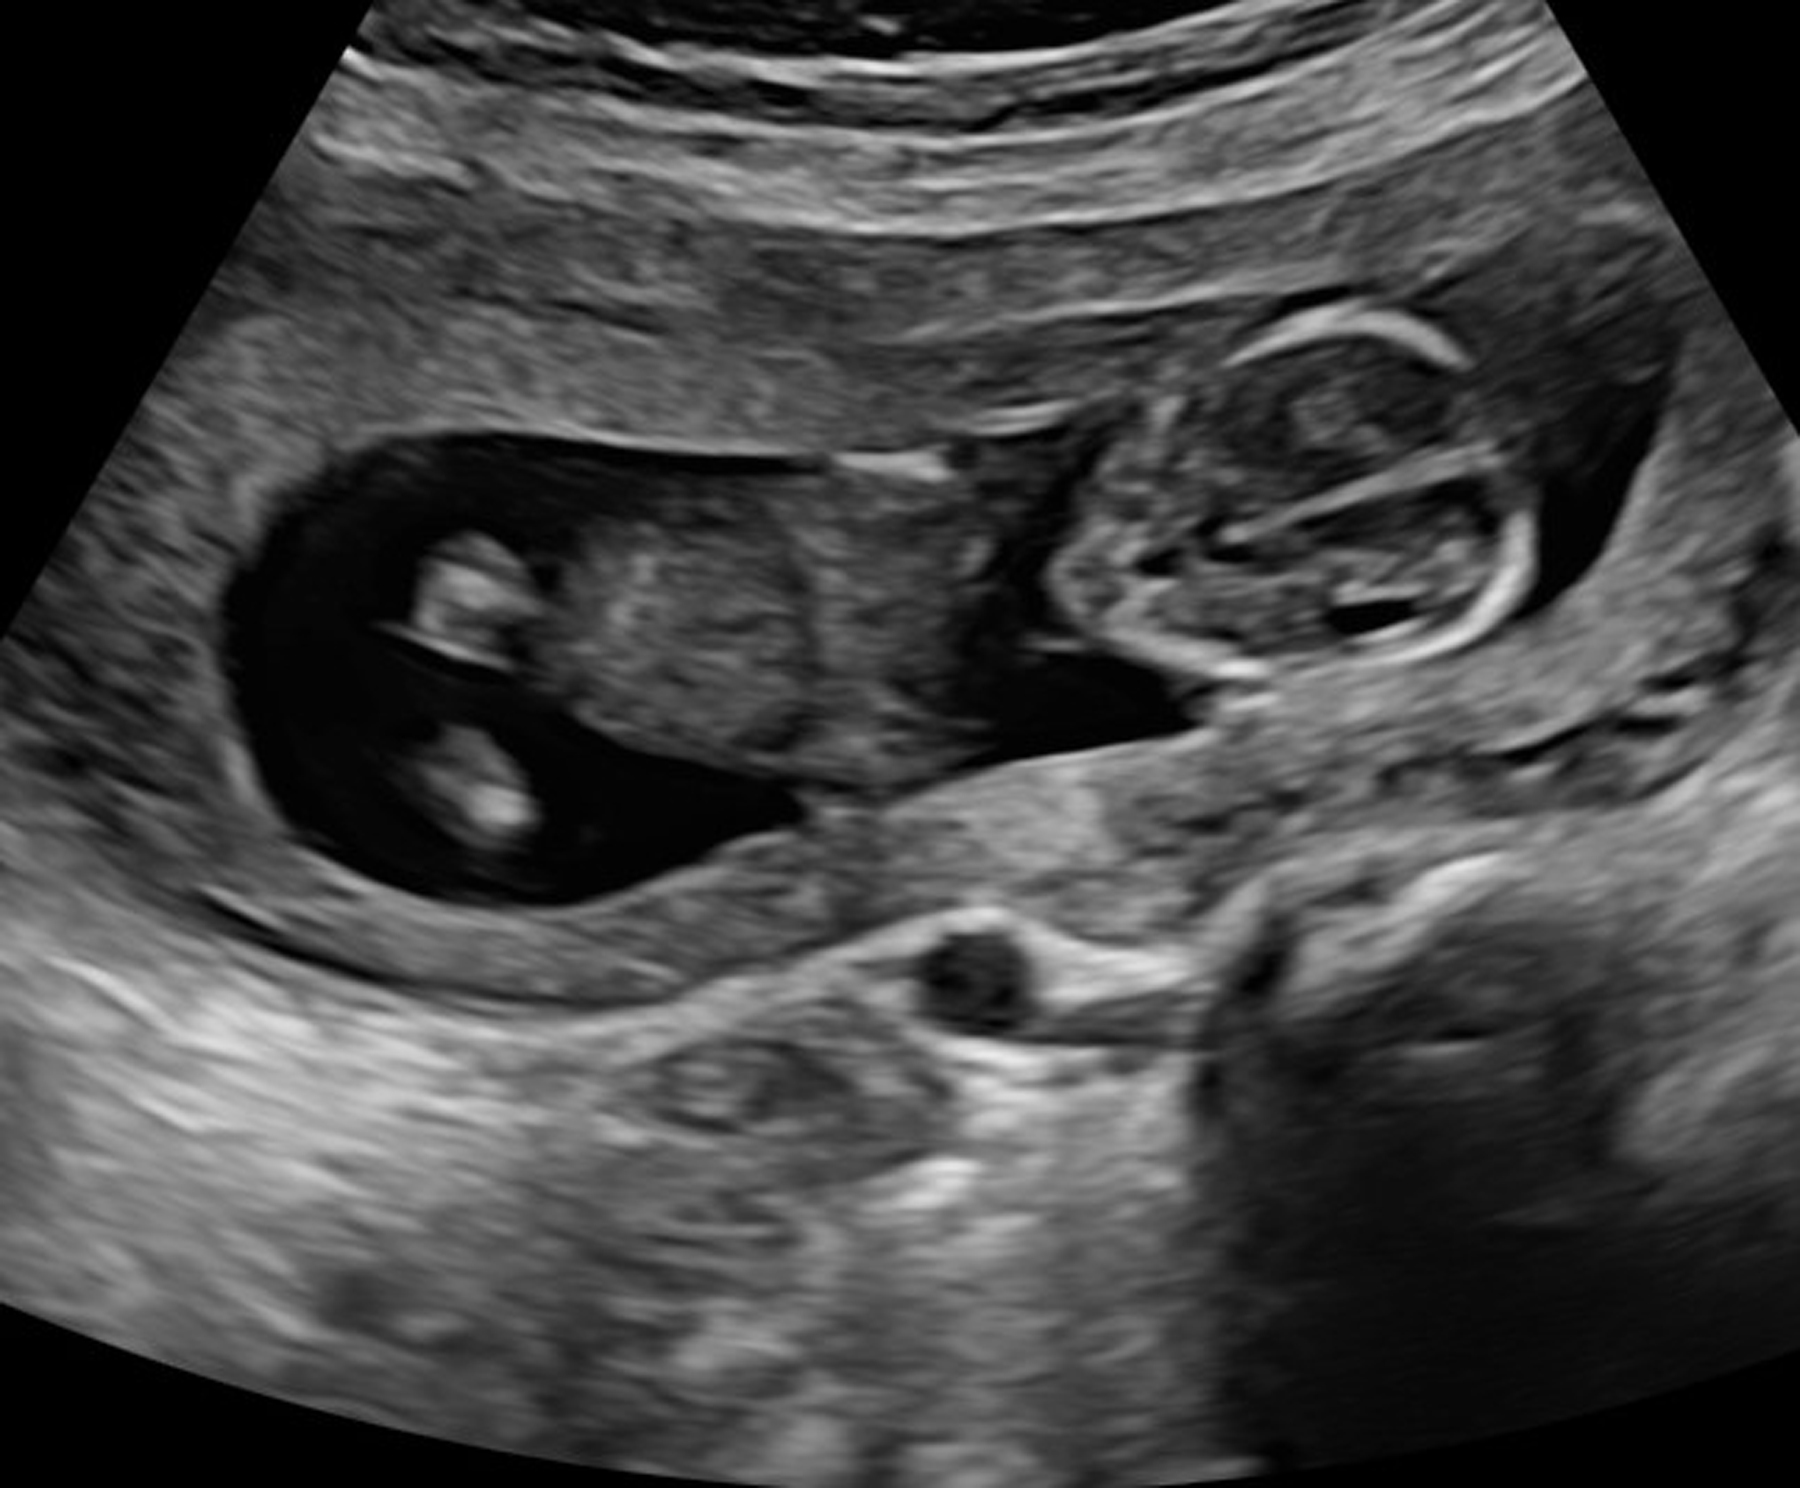

“Before you travel out-of-state … or self-manage your abortion [through ordering pills on the internet], come see us,” Bryant explained. “We can educate you on procedures, what to expect, risks, recovery time…. We can evaluate your pregnancy medically via ultrasound to confirm how far along you are, to assess whether the pregnancy appears to be viable, for an ectopic pregnancy … things like that. That message was really resonating with those abortion-minded women.”